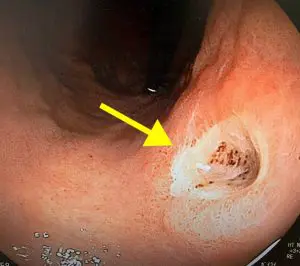

黒色嘔吐・吐血 - 福岡の苦しくない内視鏡専門医療機関福岡天神内視鏡クリニック消化器福岡博多院。

嘔吐・吐血、下血池袋消化器内科・泌尿器科クリニック東京都豊島区の消化器内科・泌尿器科。